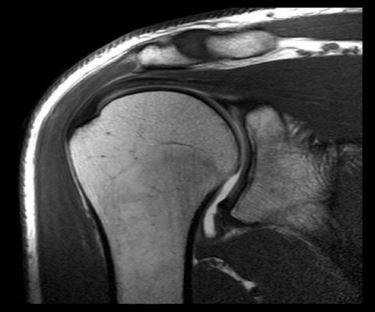

МРТ плечевого сустава. Корональные Т1-взвешенные МРТ. Переломы Хилла-Сакса и Банкарта.

Разрыв вращательной манжеты - также характерное повреждение области плеча - может быть связан как с травмой, так и дегенеративными процессами. Разрывы вращательной манжеты бывают полные и неполные. Кроме того, по МРТ плечевого сустава выделяют 3 градации, в основе которых лежит не только изменение сигнала на Т2-зависимых томограммах, но и морфологические изменения сухожилия.

МРТ. Корональная Т2-зависимая томограмма с подавлением сигнала от жира. Полный разрыв сухожилия надостной мышцы.

При МРТ плечевого сустава косвенным признаком разрыва вращательной манжеты служит высокий сигнал на Т2-взвешенных от поверхности сустава до субакромиальной (субдельтовидной) сумки. Частичные разрывы чаще всего по передней поверхности сухожилия м.supraspinatus, реже примыкая к большой бугристости или сухожилия м. infraspinatus.

МРТ плечевого сустава. Т1-взвешенная корональная МРТ. Частичный разрыв вращательной манжеты.

МРТ плечевого сустава. Т2-взвешенная корональная МРТ. Передний разрыв вращательной манжеты